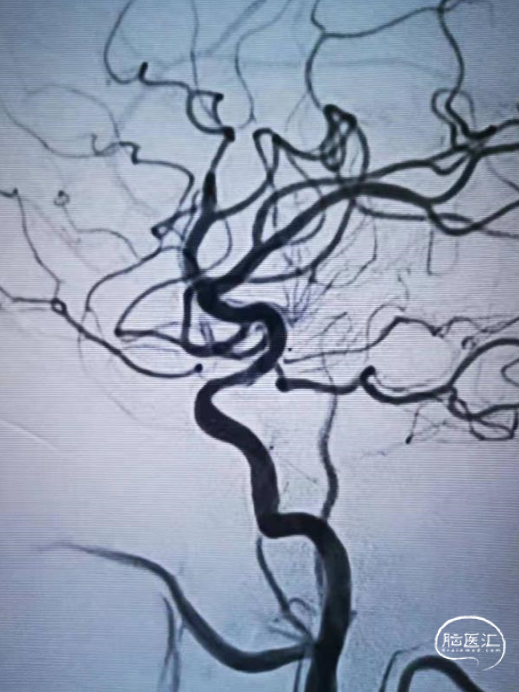

工作角度造影示:支架完全打开,贴壁良好。

术后正侧位及工作角度造影:支架贴壁良好,血流通畅。